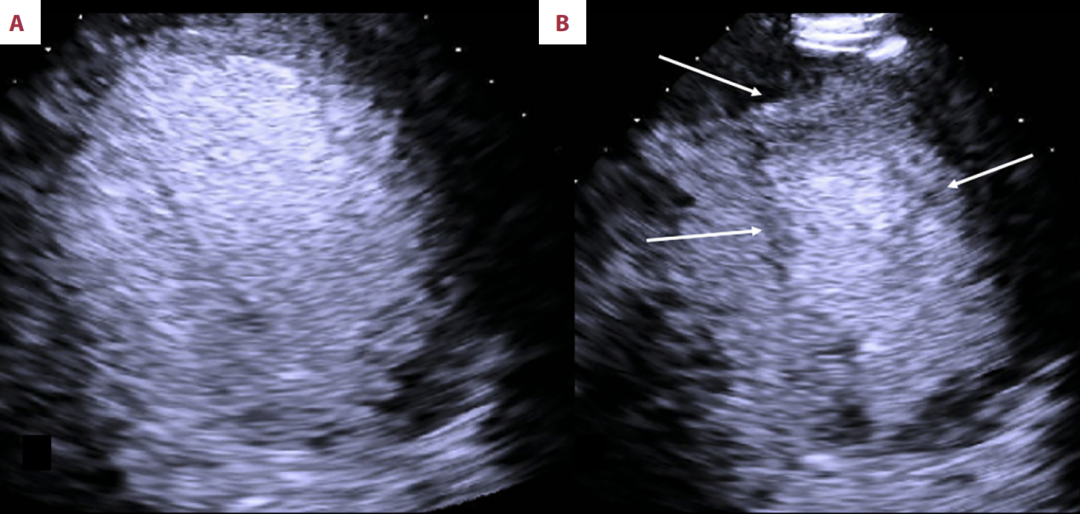

本次(2023年)发作(图1):主要表现为环周性、中远段(心尖部至中段)的运动减弱,但心尖段本身被排除在外(即心尖部仍有收缩)。这种模式被描述为“中心室型”球形变。

图1

2023年经胸超声心动图显示心尖部四腔结构;舒张期图像为A,收缩期图像为B。除心尖段外,心脏各部位的环状及中远端心肌活动明显减弱。箭头标出了前外侧及下间隔区域心肌活动缺失的情况,而心尖部仍保持正常收缩功能。